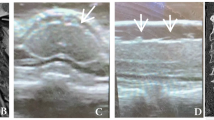

In a fluid-irrigated environment, instrument visibility issue may cause significant challenge. Figure 4 illustrates different types of challenging situations. When an instrument occupies less than 20% of the entire field of view, it is considered to have a small proportion. The dataset does not provide individual annotations for each specific difficulty, as these challenges often do not exist in isolation but rather arise from a combination of multiple factors occurring simultaneously, such as limited visibility, obstructed instrument operation, and difficulty in controlling bleeding.